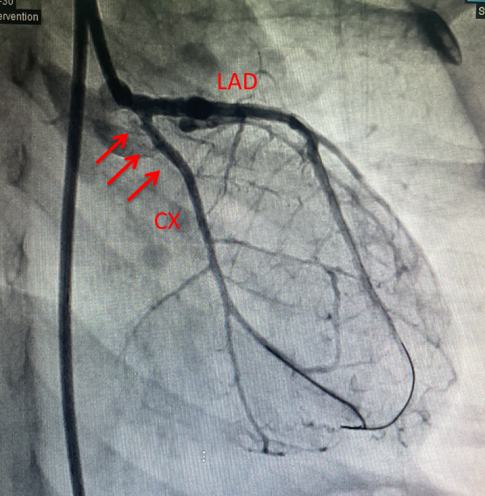

经过充分准备,11月10日,涵涵实施了冠状动脉闭塞再通及球囊扩张术。由于涵涵仅6岁,手术难度极大,但治疗小组制定了缜密的方案,历经1个半小时的手术,完美的完成了血运重建,手术后造影显示闭塞的冠状动脉完好显影(图2,图3),未见夹层及假性动脉瘤形成,整个手术操作一气呵成。

图3. 球囊扩张后造影显示左回旋支完好再通(箭头所示),

管壁光滑规整,远端血流明显增多